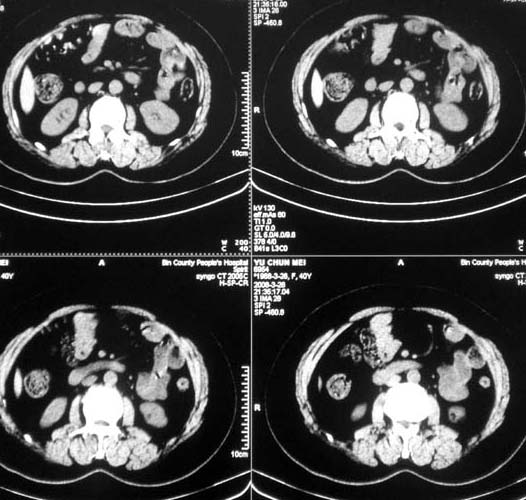

女,56岁,和上两个是同一病人,腹痛,胀痛,消化不良,五年前有血管瘤。密度减低影ct值为40hu。

肝内多发低密度影,边缘清楚,结合病史考虑:肝血管瘤可能性大,建议必须时增强扫描。